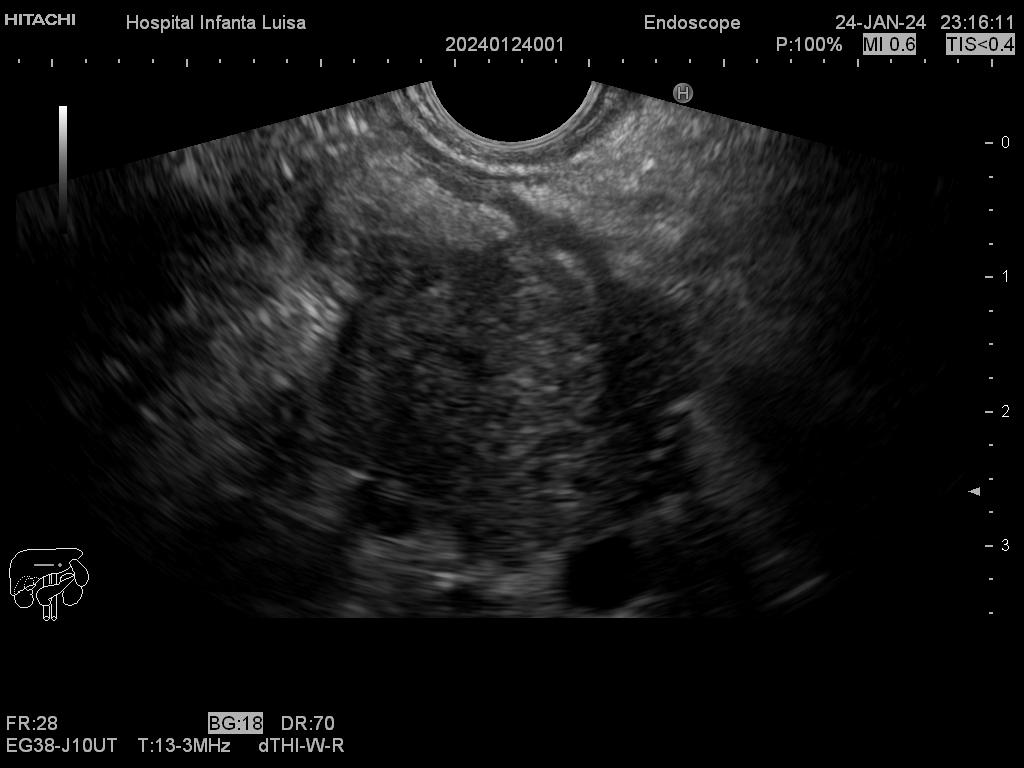

La Ecoendoscopia o Ultrasonografía endoscópica (USE) consiste en la exploración del tracto digestivo superior (principalmente), o de los últimos centímetros del tracto digestivo inferior (recto, generalmente), con un tipo de endoscopio especial que se llama ecoendoscopio.

La Ecoendoscopia, como su nombre indica, combina dos tipos de técnicas: la endoscopia y la ecografía, pues nos aporta simultáneamente una visión endoscópica (similar, aunque no igual, a la alcanzada con el gastroscopio y el colonoscopio) y ecográfica, que permite la visualización y estudio de las estructuras que quedan por fuera y están en contacto con la pared del esófago, estómago, duodeno o colon.

Mediante dicha exploración se explora minuciosamente los tramos mencionados, permitiendo valorar distintas patologías como lesiones propias de la pared de estos órganos (determinado su profundidad y extensión), o lesiones que quedan en órganos anexos, pero por fuera, de ahí la importancia de la visualización ecográfica, como páncreas, mediastino, hígado, diferentes adenopatías o masas indeterminadas previamente, entre otros.

Igualmente, es una técnica básica hoy día en el estudio de todo tipo de lesiones pancreáticas, en la determinación de formaciones subepiteliales esofágicas, gástricas (más frecuentes) o duodenales, o en el estadiaje de patología tumoral a estos niveles. La Ecoendoscopia permite la toma de biopsias a estos niveles, con control endoscópico y ecográfico, siendo una técnica de gran rentabilidad diagnóstica y seguridad.